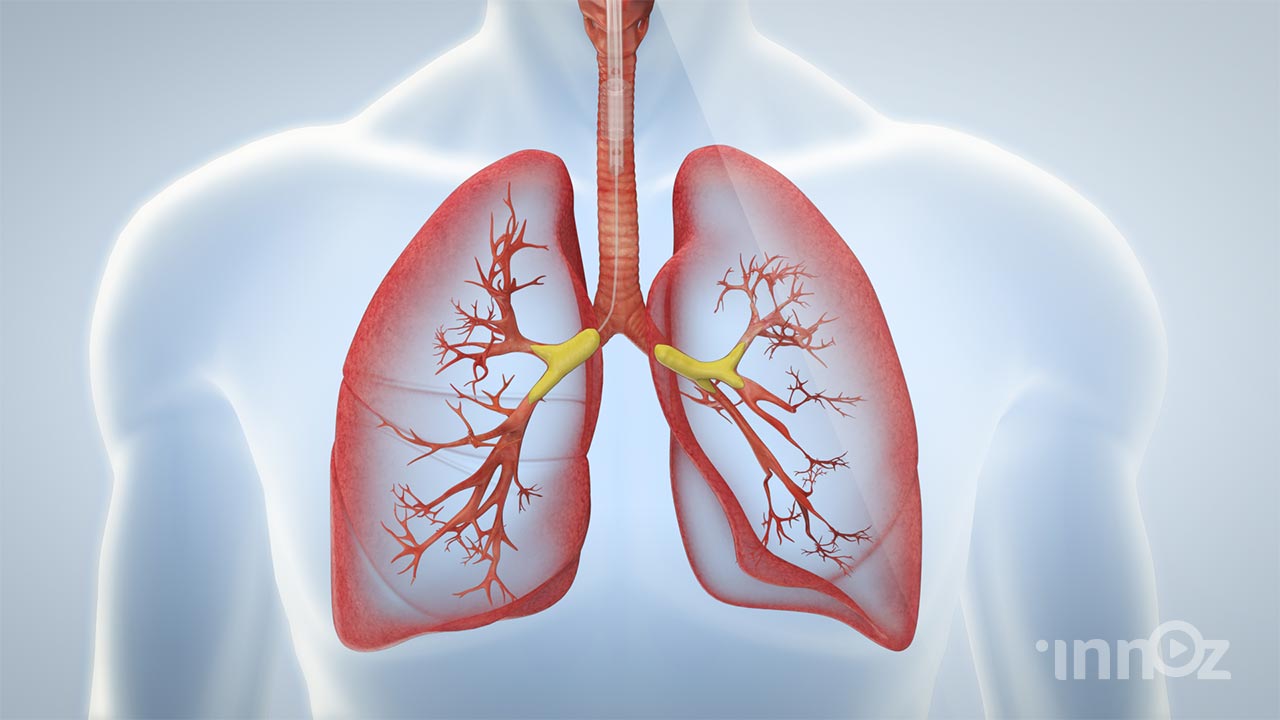

의료, 건설, 산업, VR AR, AI 등 고퀄리티 3D영상제작

이노즈는 AI영상제작, 3D영상 제작 전문기업으로, 다양한 산업 분야에 걸쳐 혁신적이고 몰입감 있는 3D 콘텐츠를 제공합니다. 제품 홍보, 건설 시뮬레이션, 애니메이션 등 맞춤형 영상으로 고객사의 가치를 시각적으로 효과적으로 전달합니다. 고품질의 3D 시각화와 창의적인 연출을 바탕으로, 고객의 목표를 실현하는 독창적이고 강력한 시각적 경험을 제공합니다. 이노즈의 포트폴리오는 고객의 아이디어를 현실로 구현한 다양한 성공적인 프로젝트로 가득합니다.

2025 파인트리 테라퓨틱스 이중특이적항체